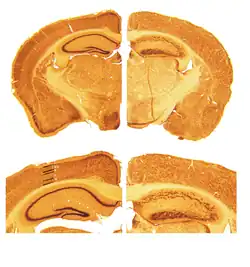

A reeler is a mouse mutant, so named because of its characteristic "reeling" gait. This is caused by the profound underdevelopment of the mouse's cerebellum, a segment of the brain responsible for locomotion. The mutation is autosomal and recessive, and prevents the typical cerebellar folia from forming.

Cortical neurons are generated normally but are abnormally placed, resulting in disorganization of cortical laminar layers in the central nervous system. The reason is the lack of reelin, an extracellular matrix glycoprotein, which, during the corticogenesis, is secreted mainly by the Cajal–Retzius cells. In the reeler neocortex, cortical plate neurons are aligned in a practically inverted fashion ("outside-in"). In the ventricular zone of the cortex fewer neurons have been found to have radial glial processes.[1] In the dentate gyrus of hippocampus, no characteristic radial glial scaffold is formed and no compact granule cell layer is established.[2] Therefore, the reeler mouse presents a good model in which to investigate the mechanisms of establishment of the precise neuronal network during development.

- Decreased cerebellar size.

First mention of reeler mouse mutation dates back to 1951.[17] In the later years, histopathological studies revealed that the reeler cerebellum is dramatically decreased in size and the normal laminar organization found in several brain regions is disrupted (Hamburgh, 1960). In 1995, the RELN gene and reelin protein were discovered at chromosome 7q22 by Tom Curran and colleagues.[18]